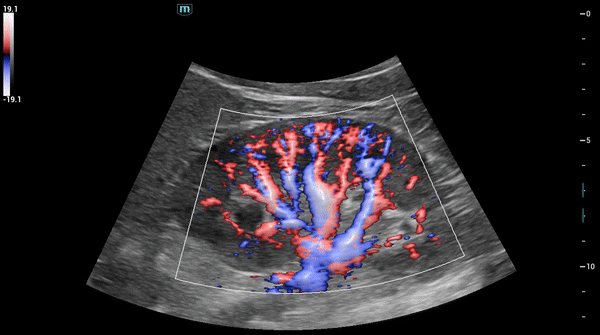

Высокоточная гемодинамика HR Flow™

Технология Mindray отображает кровоток с бо́льшим пространственным и временным разрешением даже в случае исследования мелких сосудов.

Чёткое отображение малых и перекрывающихся сосудов

Glazing Flow – метод цветового/энергетического доплеровского потока с 3D-визуализацией, дополняющий исследование гемодинамики и структуры малых и перекрывающихся сосудов.